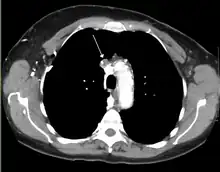

The main techniques of diagnosing SVCS are with chest X-rays (CXR), CT scans, transbronchial needle aspiration at bronchoscopy and mediastinoscopy.[5] CXRs often provide the ability to show mediastinal widening and may show the presenting primary cause of SVCS.[5] However, 16% of people with SVC syndrome have a normal chest X-ray. CT scans should be contrast enhanced and be taken on the neck, chest, lower abdomen, and pelvis.[5] They may also show the underlying cause and the extent to which the disease has progressed.[5]